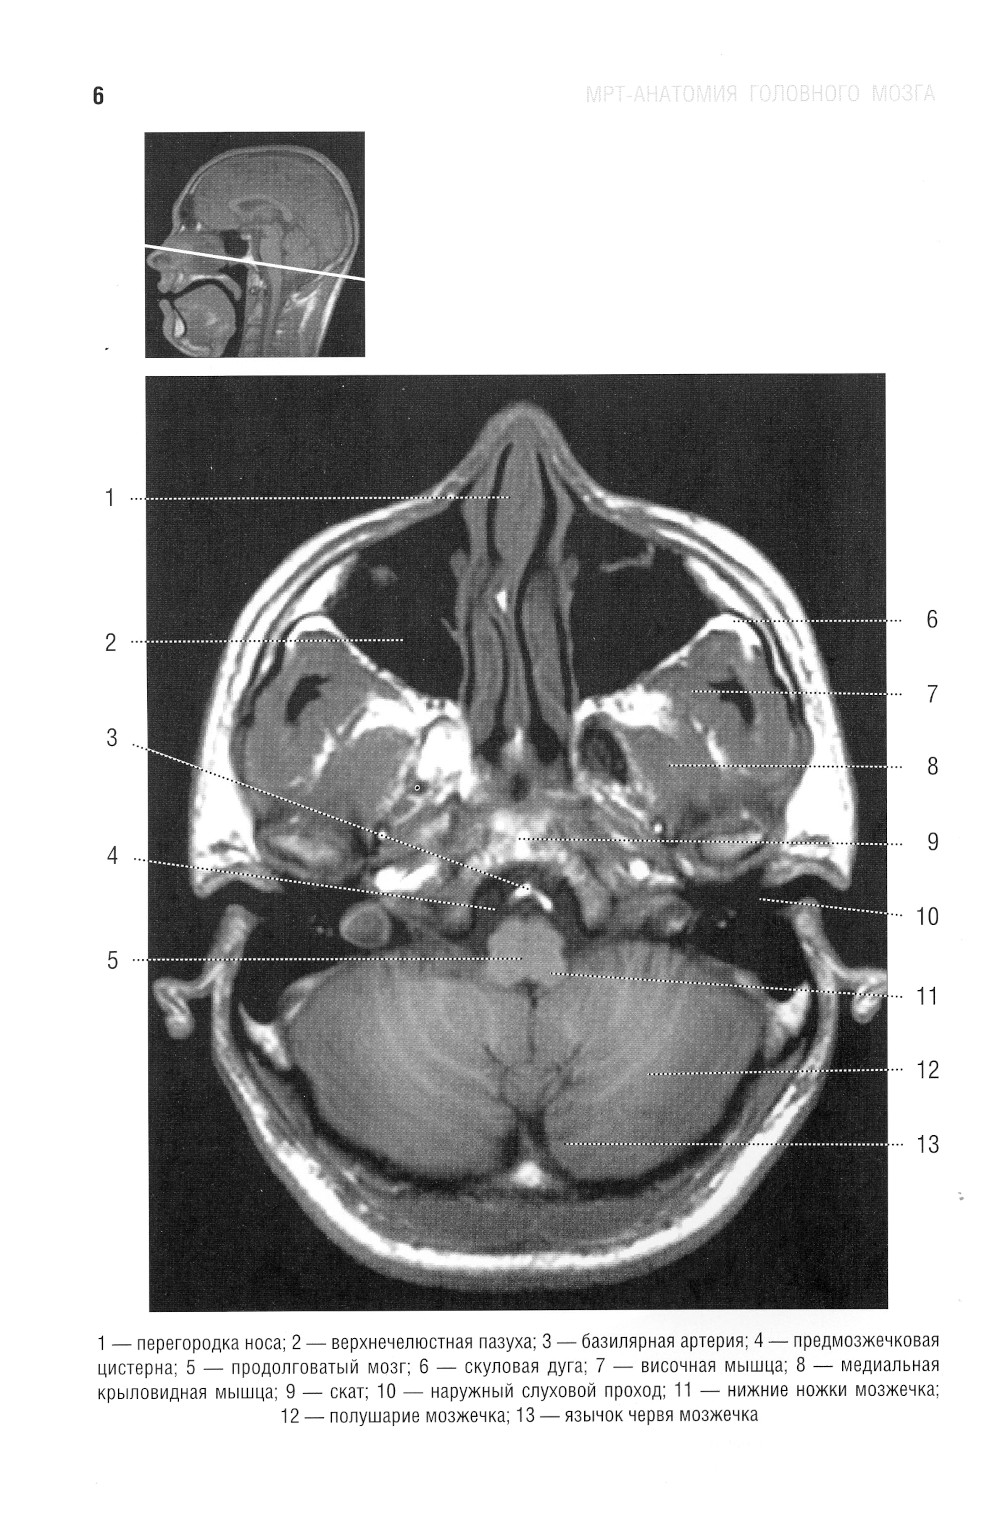

В руководстве представлена нормальная анатомия головного мозга и позвоночника по данным МРТ- и КТ-исследований. MPT-изображения головного мозга отражены в трех взаимно перпендикулярных плоскостях. Отдельная глава посвящена визуализации и нормальной анатомии сосудов головного мозга, в том числе с изображениями, получаемыми при бесконтрастной магнитно-резонансной ангиографии. Для врачей-рентгенологов, специалистов КТ и МРТ, невропатологов, нейрохирургов, а также врачей смежных специальностей. Руководство рекомендовано для обучения студентов медицинских вузов, а также может использоваться в системе последипломного профессионального образования.| Издательство | Элби |